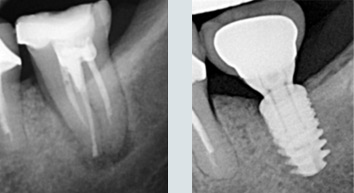

Des dents qui manquent.

Les dents sont remplacées par des couronnes individuelles sur implants. Sourire final.

Une situation de pertes dentaires multiples et infections sous des racines naturelles.

Final : traitements de racines effectués et dents manquantes remplacées.